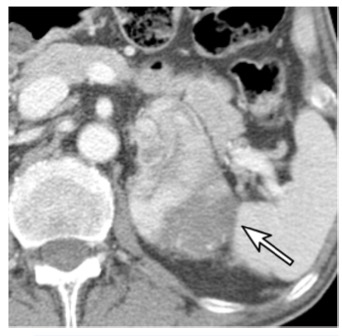

圖 一名67歲的男性,患有乙狀結(jié)腸癌。增強(qiáng)CT圖像顯示左側(cè)腎上腺有一個74毫米的結(jié)節(jié)(箭頭)。腎上腺切除術(shù)后,該結(jié)節(jié)被證實為腎上腺皮質(zhì)癌。結(jié)腸癌經(jīng)息肉切除術(shù)后確認(rèn)為PT1期